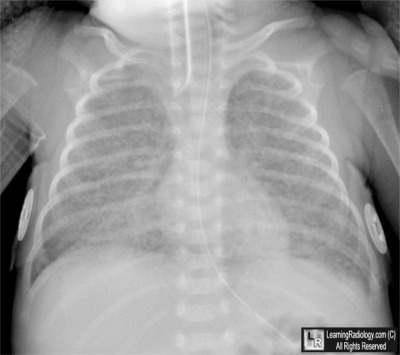

Frontal Radiograph of the Chest

3. Bronchopulmonary dysplasia

Bronchopulmonary dysplasia